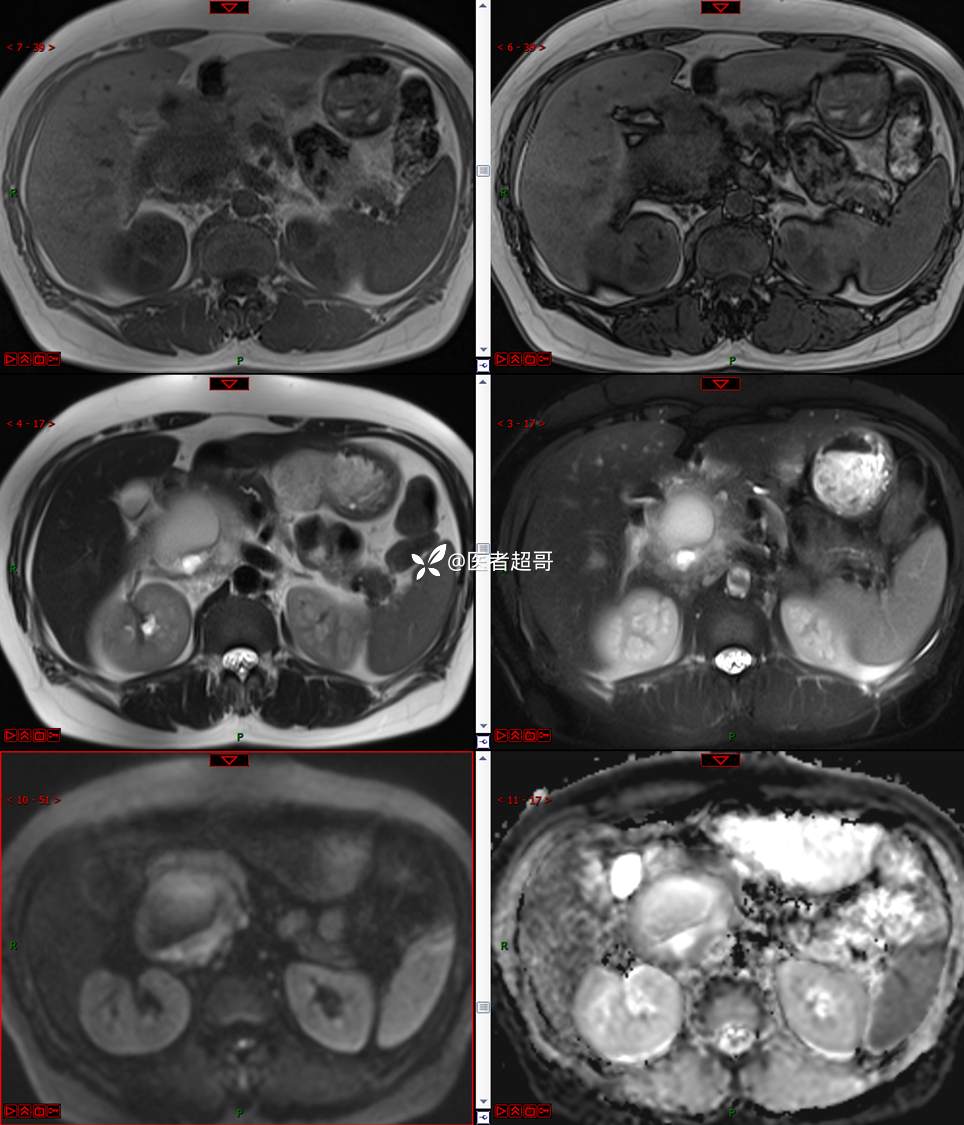

【影诊笔记671】定位有难度,究竟是腹腔内or腹膜后,请先定位,再定性!有结果~~~

hyy838 推荐女,52岁

主诉:查体发现腹部肿物1周。

现病史:患者1周前于我院查体发现右侧腹部肿物,无腹痛、腹泻、便血,无恶心、呕吐,患者为求进一步治疗,遂就诊于我院,门诊以“腹部肿物”收入院。患者自患病以来睡眠可,精神可,饮食可,小便无明显异常,体重无明显变化。

专科检查:腹部平坦,腹肌软,无压痛及反跳痛,无包块,肝脾无肿大,Murphy征阴性,腹部叩鼓,肝脾双肾无叩痛,移动性浊音阴性,肠鸣音正常。我院 肝胆胰脾肾彩超提示:脂肪肝、腹腔内囊实性团块,建议进一步检查。